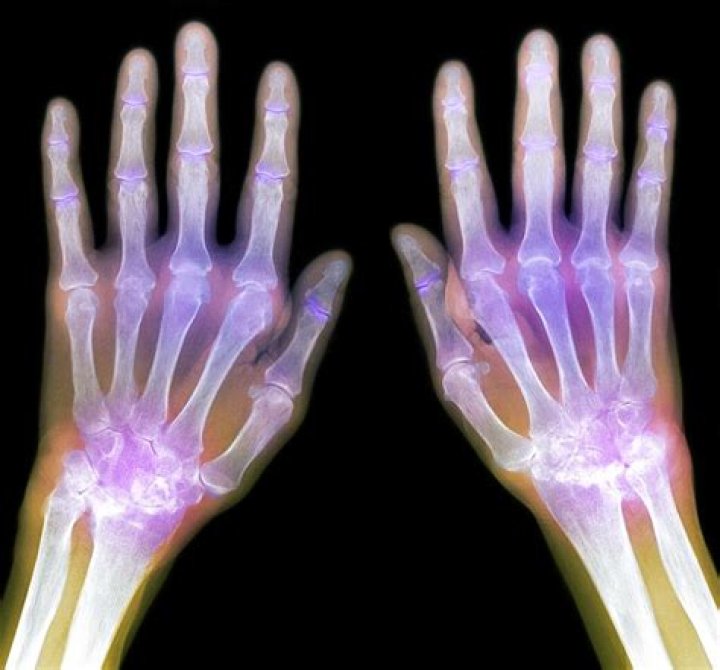

X-rays are often a good tool for determining if arthritis exists and, specifically, what type. Common types of arthritis include rheumatoid arthritis, psoriatic arthritis, and osteoarthritis.

Will xray show arthritis in hands?

Hand arthritis is typically diagnosed with x-rays. Osteoarthritis (OA) is the most common form of arthritis. This is caused by wear-and-tear, genetics, injuries, and it is often a normal part of the aging process.